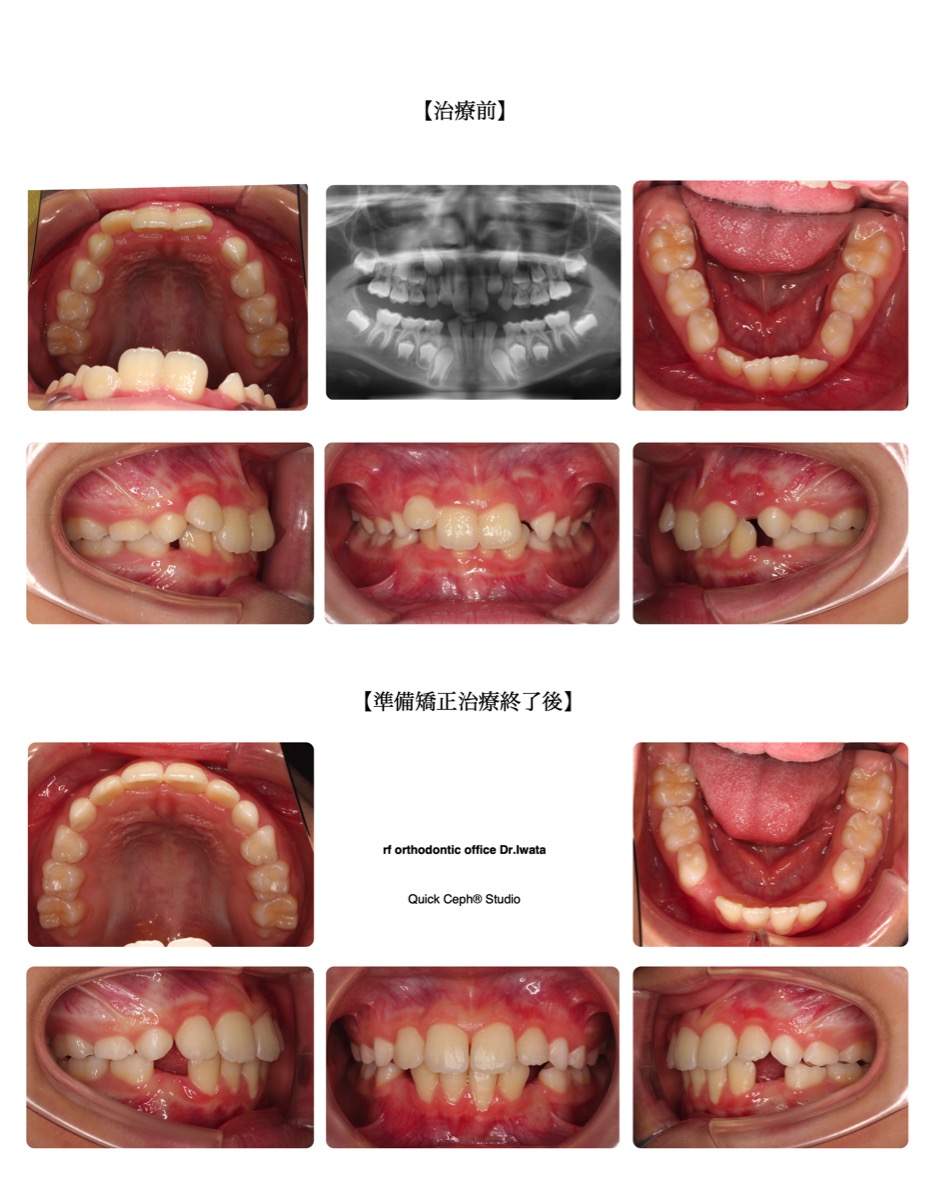

case1

叢生(でこぼこ)

歯が一列に並びきらず、デコボコになっている噛み合わせ。